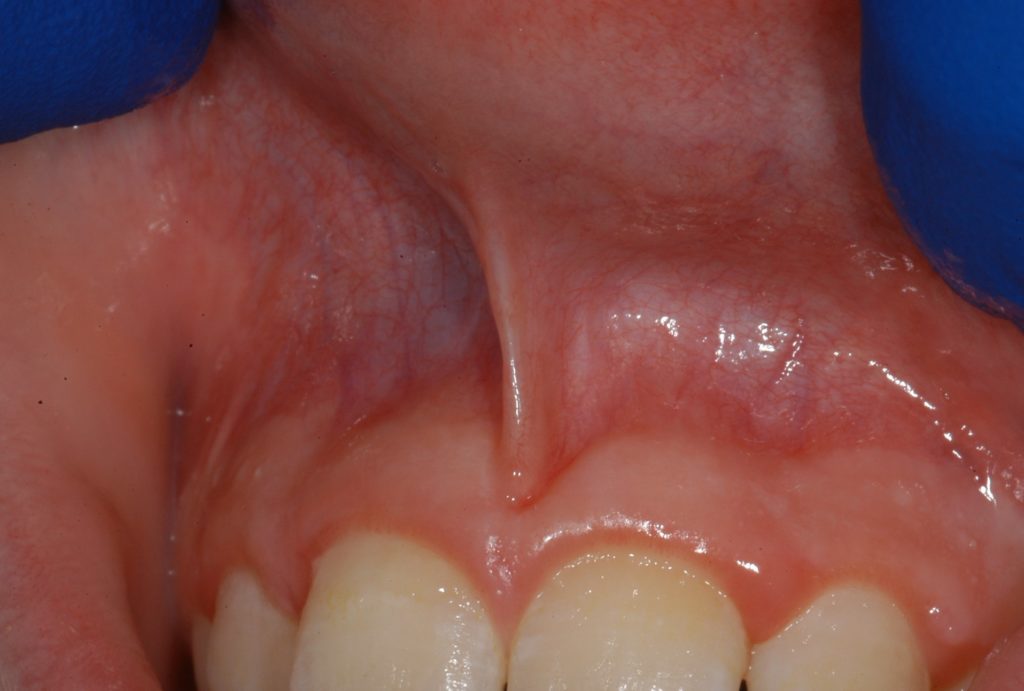

cirugia del frenillo labial superior

La cirugía del frenillo labial superior se realiza en pacientes jóvenes por función o por estética. Descubre en qué casos es conveniente realizar este procedimiento y en qué consiste.

El frenillo labial es una banda de tejido fibroso que parte de la cara interna del labio y va a insertarse sobre la línea media de la encía adherida.

El frenillo labial superior es una banda de tejido fibroso que parte de la cara interna del labio y va a insertarse sobre la línea media de la encía adherida interincisal del maxilar superior.